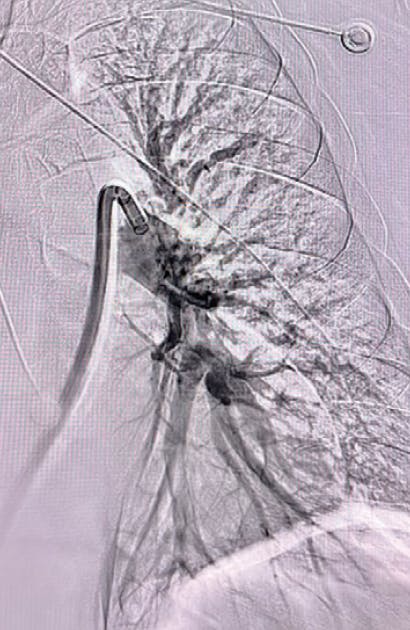

Figure 1. Right lobe initial angiogram.

Figure 2. Left lobe initial angiogram.

Figure 1. Right initial angiogram.

Figure 2. Left initial angiogram.